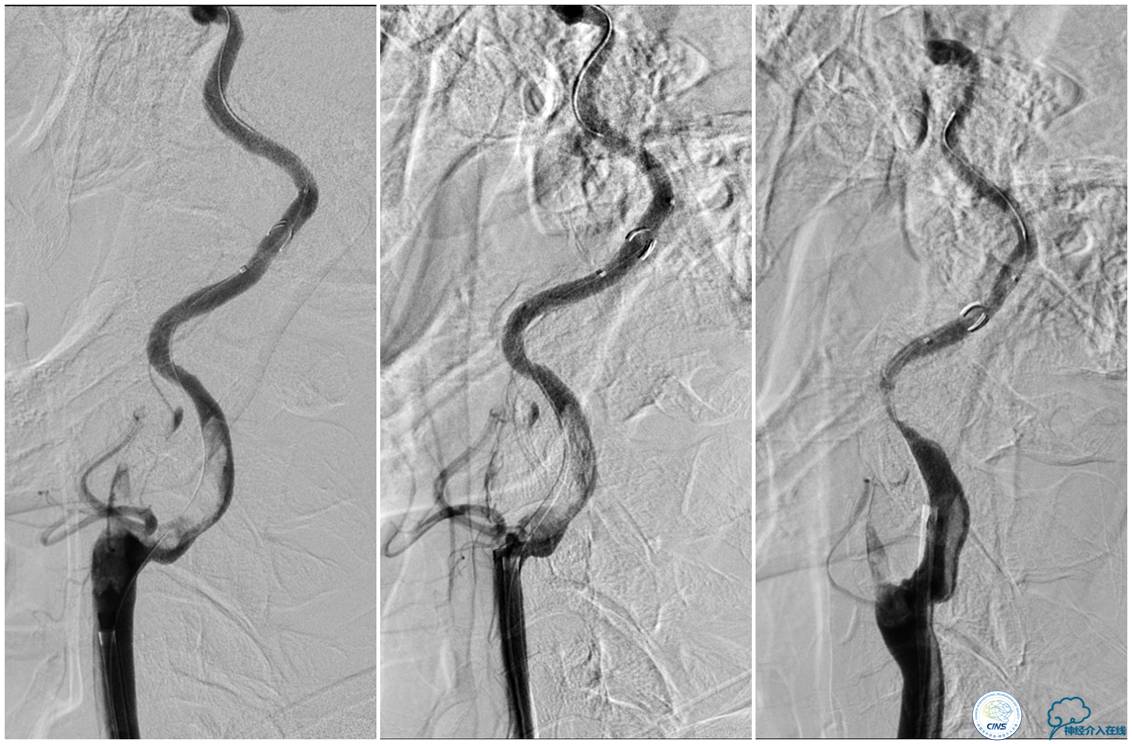

▼21:27穿刺成功,TOT 297min。左侧颈总动脉末端、颈内动脉起始部及颈外动脉起始部长条状血栓形成,随血流晃动,同侧大脑中动脉、大脑前动脉显影良好。

▼选用NAV 6 7.2 mm远端保护装置置于左侧颈内动脉C1段末端,将8F Gulding先后置于颈总动脉及颈内动脉开口部,50 ml注射器反复抽吸,抽出大量血栓。

▼颈总动脉及颈内动脉血栓抽吸完全,远端血流较前好转,TICI 3级。